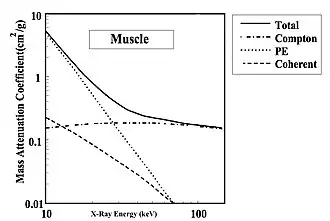

- Let's first consider the attenuation situation for muscle tissue, as shown in Figure 3.6, where its Mass Attenuation Coefficient is plotted against X-ray energy[6]. This coefficient is a measure of the attenuating ability of a material, where ‘attenuation’ is the term used to express the effects of both absorption and scattering processes.

- The attenuation due to the photoelectric effect is seen to decrease almost linearly with X-ray energy and becomes less than that of the Compton effect above about 25 keV. The Compton effect itself is seen to be relatively constant at all X-ray energies at about 0.2 cm2/g. And finally, coherent scatter is seen to have a relatively low value and to decrease with X-ray energy. We can therefore conclude that, for muscle, the major interaction process is the photoelectric effect at low X-ray energies and the Compton effect becomes dominant at higher energies.